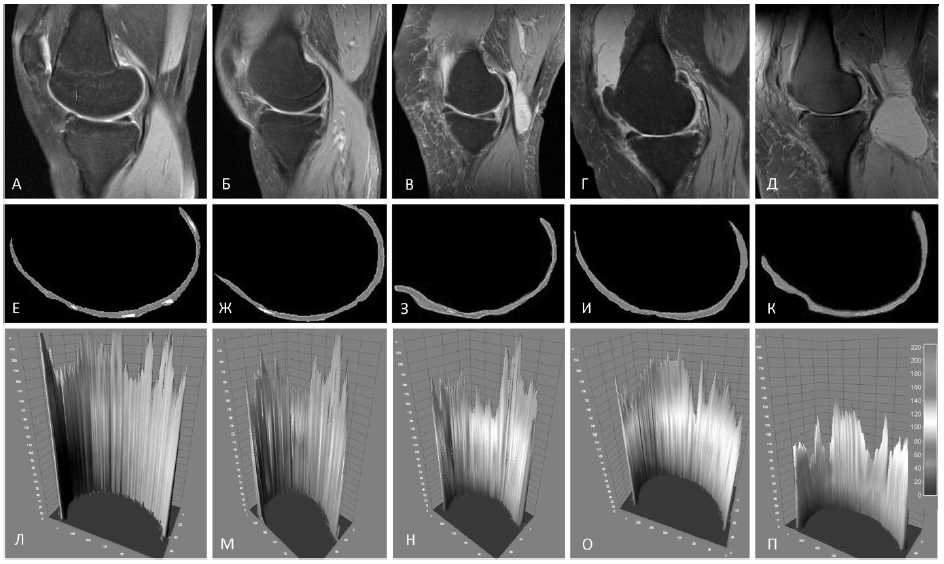

Всем пациентам, включенным в исследование, выполнена МРТ коленных суставов на высокопольном томографе Siemens Magnetom Symphony с напряженностью магнитного поля 1,5 Тесла. Для оценки изменений костной ткани использованы T1-взвешенные изображения с жироподавлением (T1). Для оценки хрящевой ткани взяты изображения Proton Density Fat Saturated – протонная плотность с подавлением жира (PDFS). Оценку МР-изображений осуществляли по протоколу Whole-Organ Magnetic Resonance Imaging Score (WORMS) [12], в рамках которого оценивали состояние СХК, суставного хряща, остеофитов. Размеры субхондральных кист (СРК) оценивали по среднему значению от всех измерений у данного пациента. Для оценки протонной плотности ручным способом производили сегментацию PDFS-взвешенных изображений области медиального мыщелка коленного сустава, как показано на рисунке. После сегментации с целью улучшения градиентного восприятия на область интереса накладывали 16-цветную маску. Плотность протонов оценивали по 3D-гистограмме по шкале от 0 до 255. Процедуру сегментации и анализа осуществляли с помощью программного обеспечения ImageJ.

Рис. Сегментация PDFS-взвешенных магнитно-резонансных томограмм и спектры протонной плотности суставного хряща: фрагменты А–Д – МРТ коленного сустава в области медиального мыщелка бедренной кости; фрагменты Е–К – сегментация изображений суставного хряща; фрагменты Л–П – спектры протонной плотности; фрагменты А–Л соответствуют норме, Б–М – I стадия ОА, В–Н – II стадия ОА; Г–О – III стадия ОА; Д–П – IV стадия ОА

Оценка распределения PD в суставном хряще (см. рисунок) показала, что при I стадии ОА наблюдалось уменьшение плотности H+ в периферийной зоне СХ, но сохранялось в контактной части, испытывающей максимальные статодинамические нагрузки. Анализ спектра H+-распределения на II стадии ОА показал значимое прогрессирующее снижение пиков плотности в участках СХ, подвергающихся меньшим нагрузкам, с сохранением высоких спектральных пиков в области повышенного трения. III стадия гонартроза характеризовалась снижением всего плана H+-спектров, особенно выраженно в нагрузочных участках СХ. При терминальной IV стадии ОА наблюдалось глобальное снижение интенсивности PD по всей поверхности хрящевой пластинки.